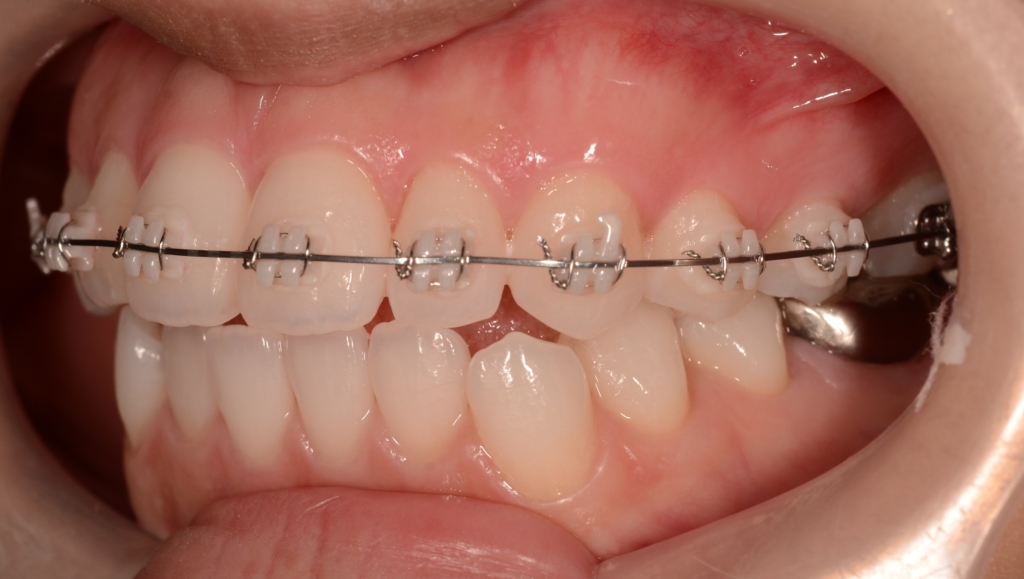

噛み合わせがしっかりしたところで、上下とも第一小臼歯を抜歯して前歯を後方へ最大限に引っ込めて行きます。

当初は最大限に前歯を引っ込めて行く予定だったのですが、治療途中で患者さんから「このくらいで良いかも!?」という状態評価が出てきました。

そこで、その時点からは力を加減して残る隙間を閉じて、噛み合わせを確立するように、治療プランに修正を加えて進めて行きました。